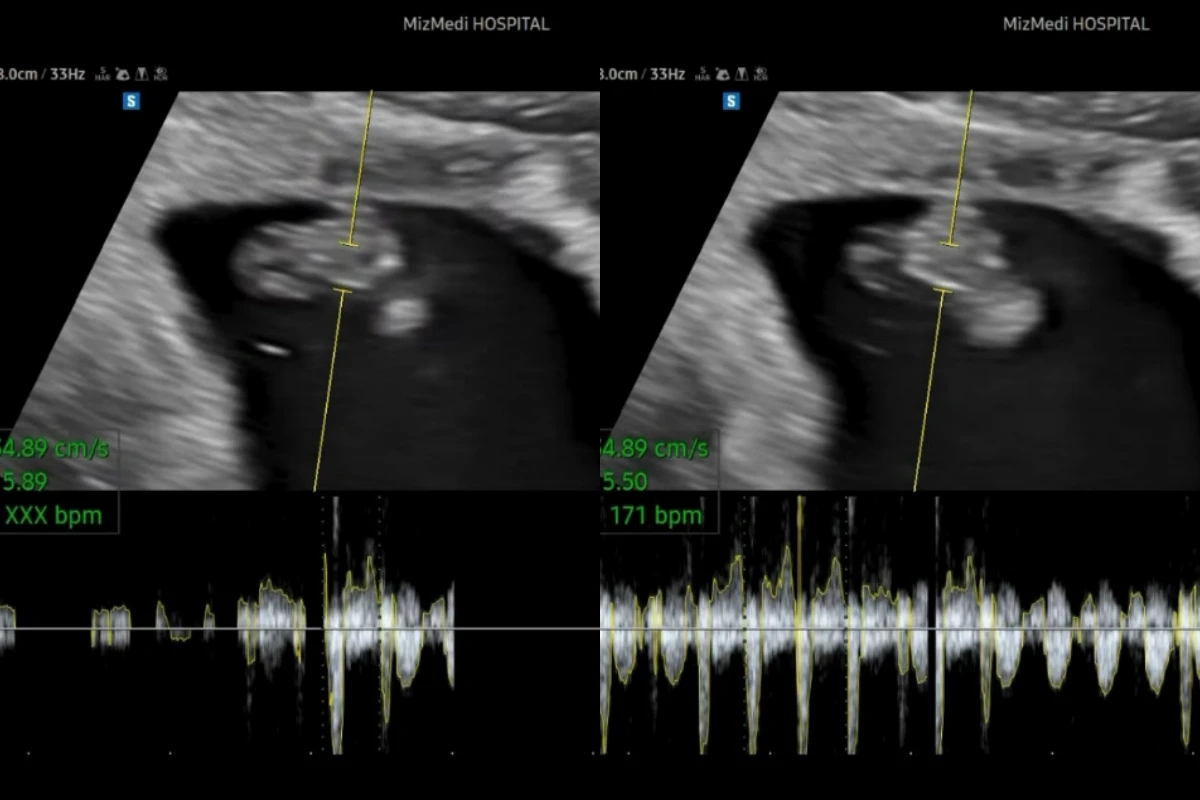

17일 아야네는 자신의 계정에 최근 촬영한 둘째 초음파 영상과 함께 이지훈과 아야네의 사진을 AI로 합성한 아기 얼굴을 공개했다.

또 아야네는 "하여튼 저보다 제 팔로워분들이 궁금해하실 것 같아서 심장소리 가져왔어요ㅋㅋㅋ!! 들으시고 댓글에 남겨주시거나 투표해 주세요. 과연 제2의 이지훈은 나올것인가….!!ㅎㅎ"라고 덧붙였다.